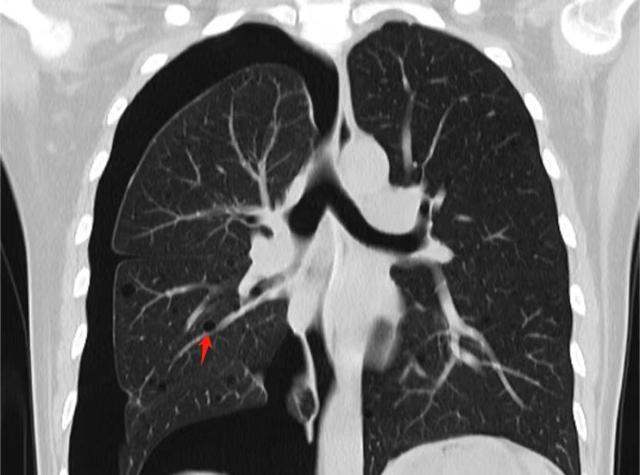

(▲术前胸部CT显示:右侧气胸,双肺囊泡样改变就像一个个大小不一的”肥皂泡“(如箭头所示))

为了查明反复发生气胸的原因,徐女士先后前往北京、上海等地的大医院就诊,最终确诊为“肺淋巴管腺肌瘤病”。这是一种极为罕见的多系统肿瘤性疾病,好发于育龄期妇女,发病率约为1/100万-18/100万。如不及时治疗,会引起呼吸困难,甚至因呼吸衰竭危及生命。

“肺淋巴管腺肌瘤病是一种罕见病,病变导致双肺呈囊泡样改变,肺表面任何一处囊泡破裂,都可导致气胸的发生。”张志功副主任医师表示,肺淋巴管腺肌瘤病患者第一次出现气胸的时候就建议采用胸膜固定,以减少后续气胸复发几率。但部分患者担心胸膜固定后会影响后续肺移植手术而拒绝。